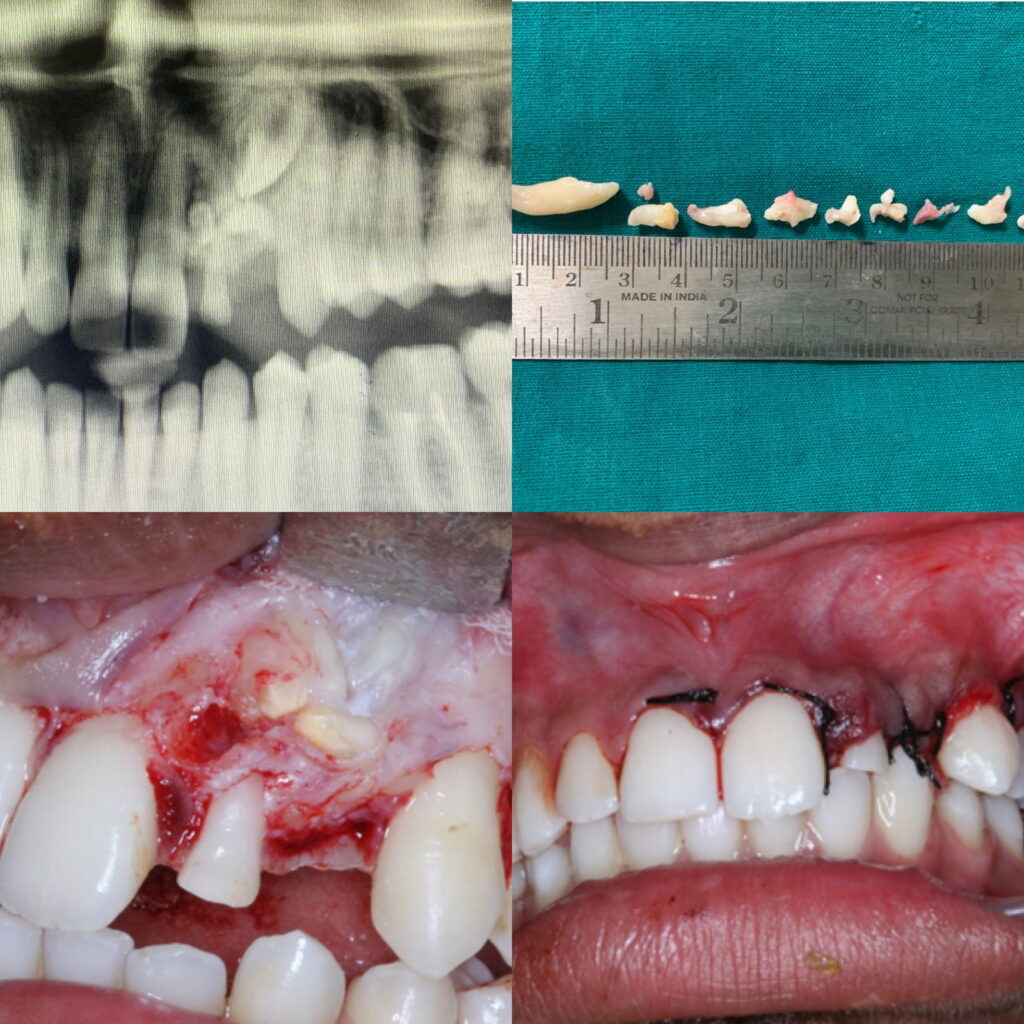

Case of multiple compound odontome in 18 year old male patient.